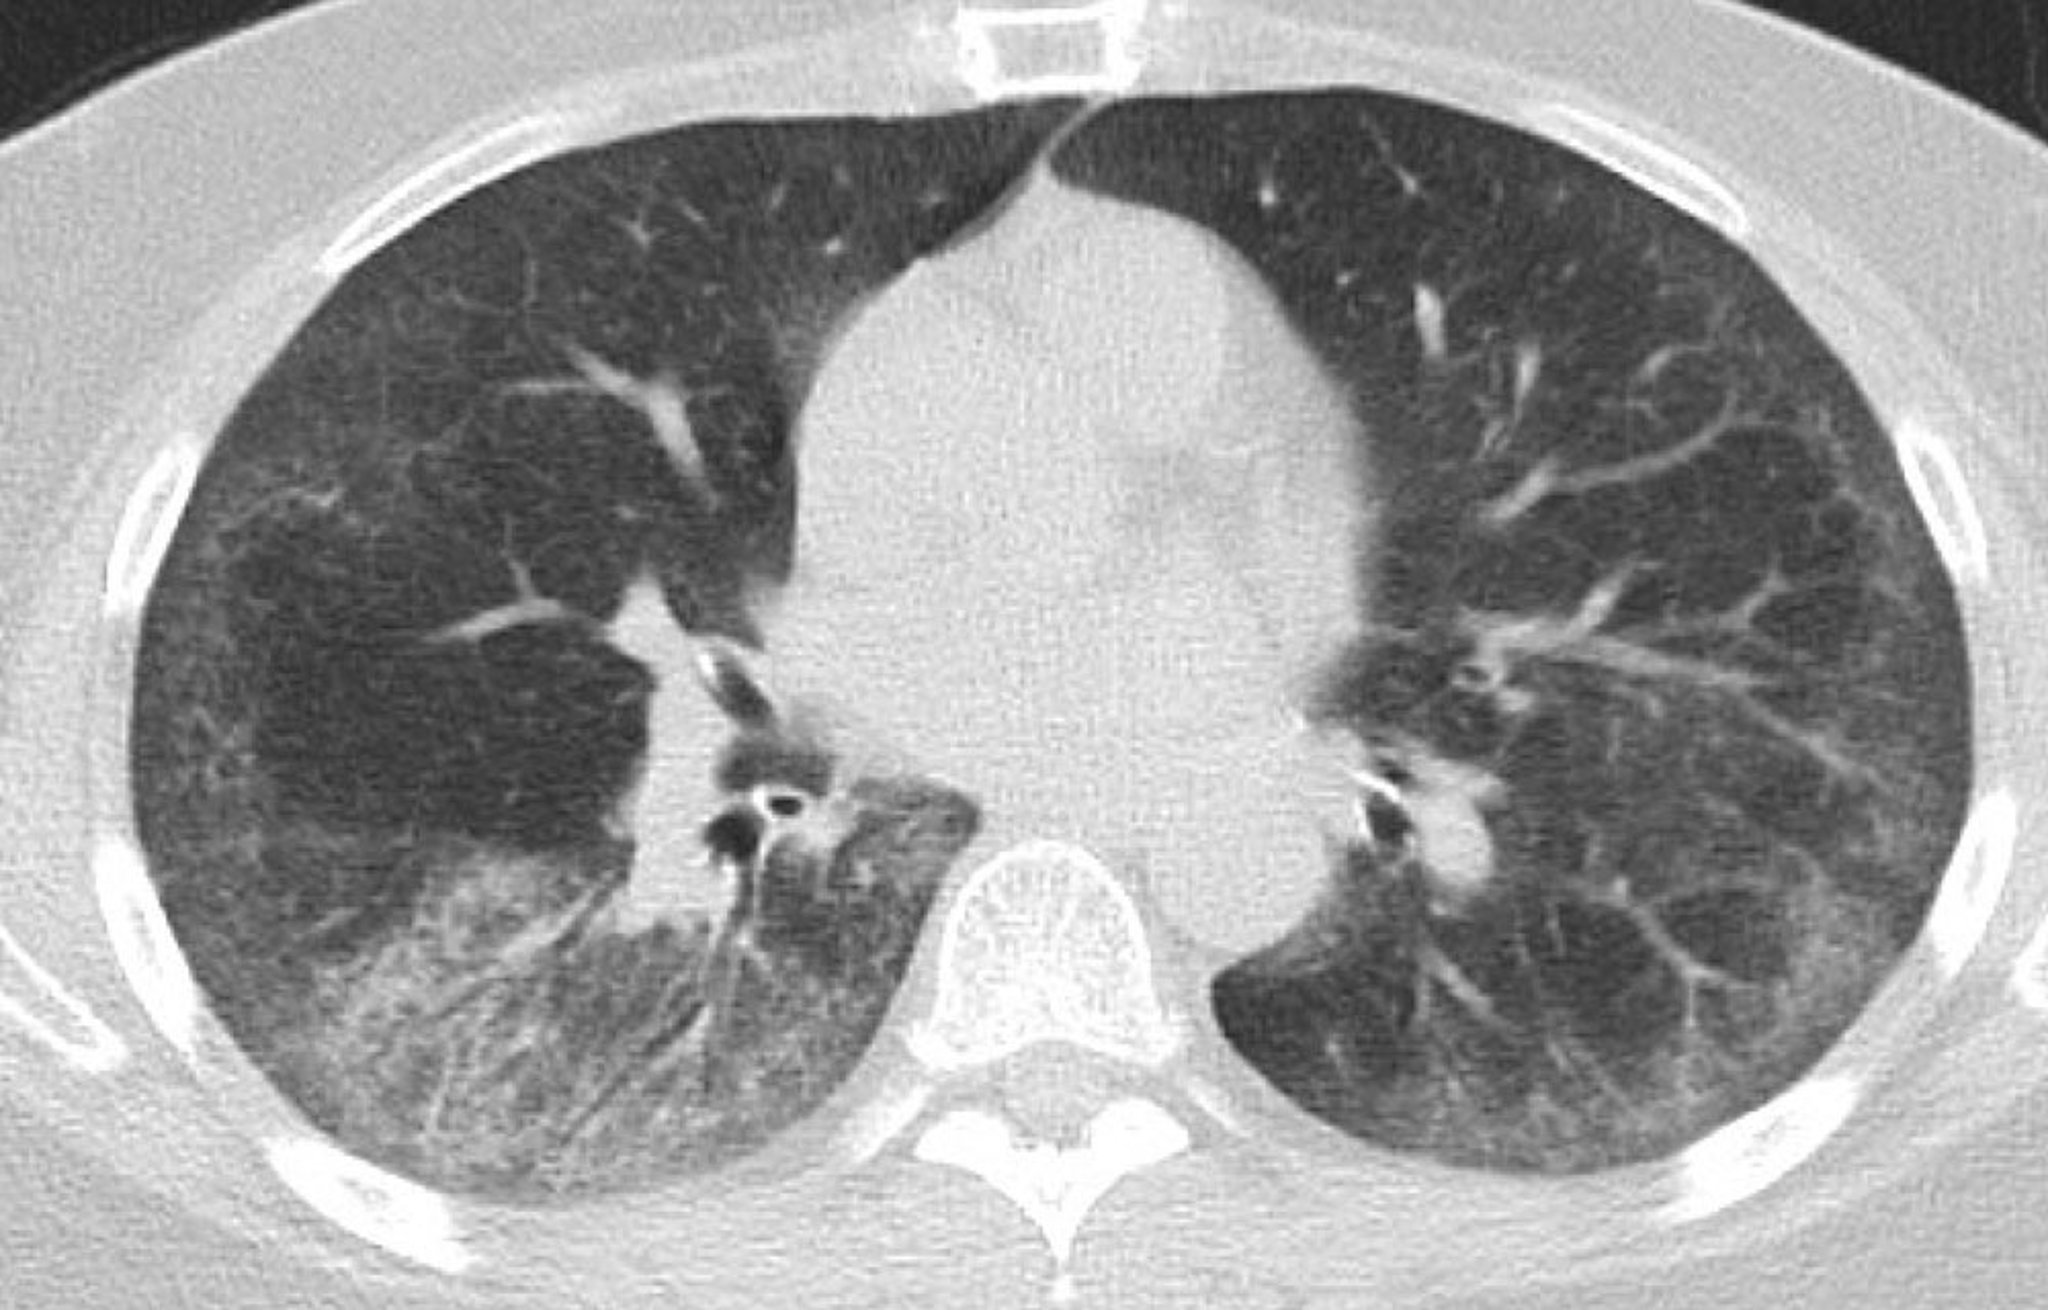

Enfermedad pulmonar intersticial (TC de tórax)

Esta TC muestra opacidades bilaterales simétricas en vidrio esmerilado en el lóbulo inferior con áreas de reticulación subpleural fina; bronquiectasias leves por tracción en ambos pulmones con preservación subpleural y algunos ganglios linfáticos torácicos dispersos.

Photo courtesy of Kinanah Yaseen, MD.